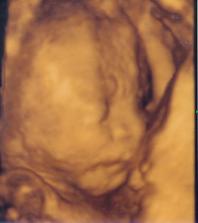

bubadlo27

27. mar 2008

Martinko a Sofia 2